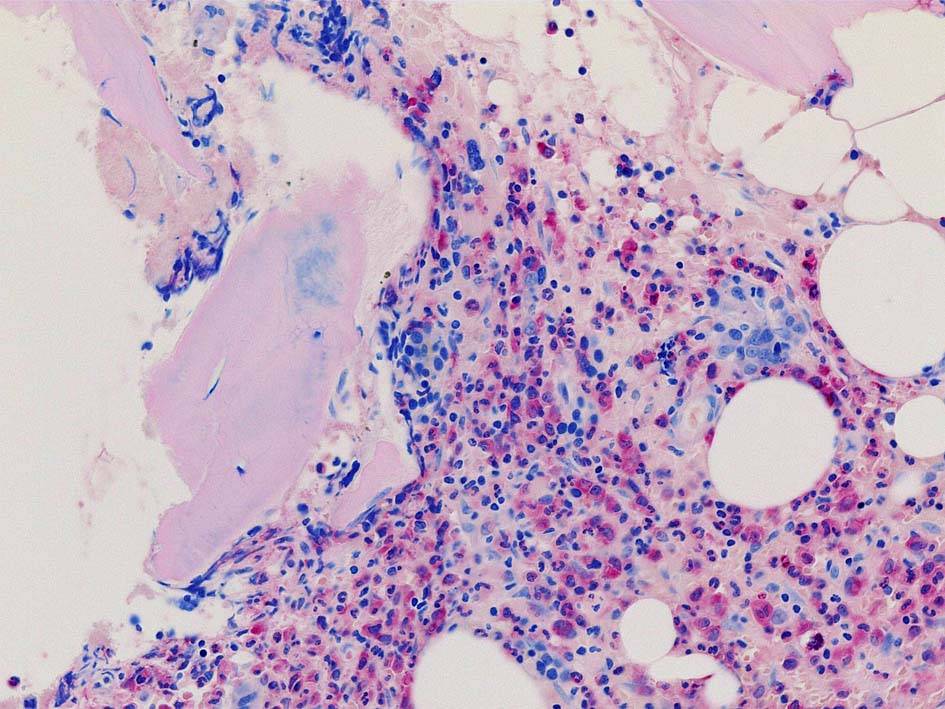

Case02; Meylofibrosis, overt fibrosis

77year-old female. 40歳時polycythemia veraと診断されていた.

黒染する弾性線維の増生のほか, 赤く染まる膠原線維の増生が確認される. MF-2 fibrosis. 鍍銀染色の核染色をすると膠原線維の赤染がわからなくなるので行わない.